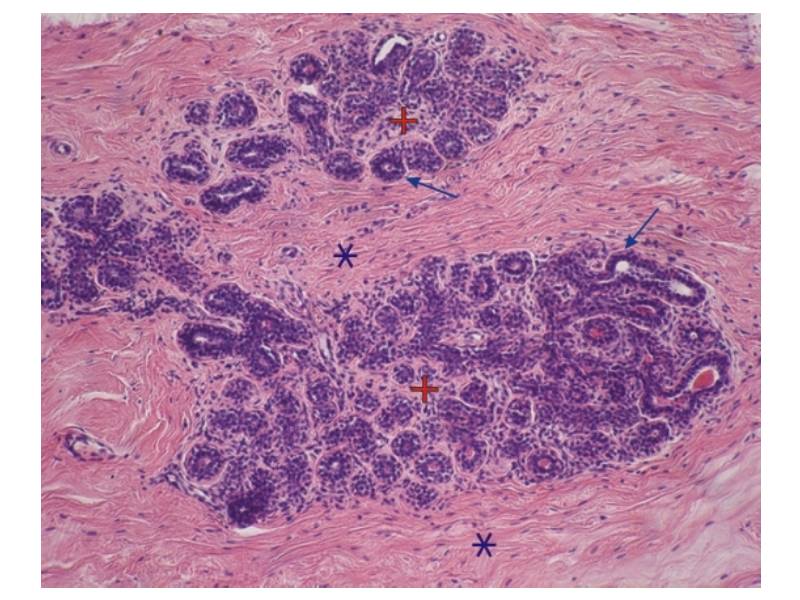

Mammary gland and digestive track

Histology